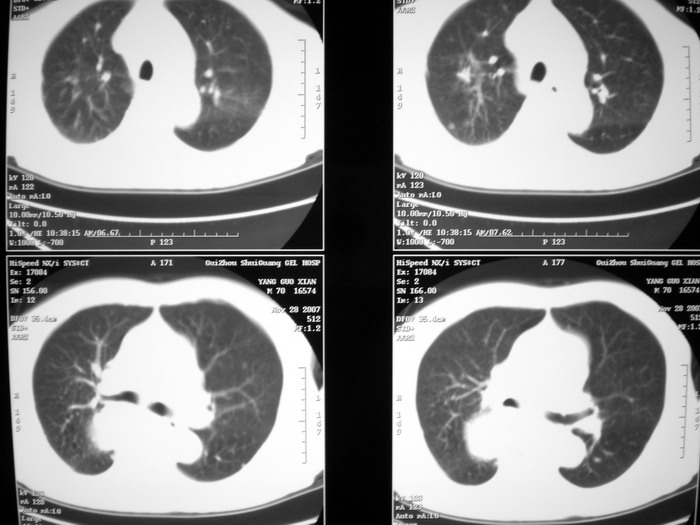

m、70y,反复咳嗽2月。请各位同仁给定位1、(肺?,纵隔?)2、定性。感谢!!

右后纵隔占位,气管前腔静脉后淋巴结肿大:1.神经源性肿瘤,2.恶性淋巴瘤?

右下肺纵隔旁较大 均匀密度肿块,部分边缘植入纵隔,气管明显受压 变形。支持:后纵隔肿瘤!首选:神经源性!不支持肺内肿瘤原因:1 肿瘤位于下叶支气管及背段支气管开口区,但未侵犯支气管,只是受压表现。2 纵隔内未见肿大淋巴结。3 肺内未见阻塞性肺炎。

考虑奇静脉食管隐窝战位,肺癌并纵隔淋巴转移

支持后纵隔肿瘤,病灶大体呈“滴状”与支气管关系密切,考虑:1.高密度支气管囊肿,2.神经纤维瘤。增强有鉴别意义。

肺上有多个小结节哦,考虑转移,那就应该是恶性的啊